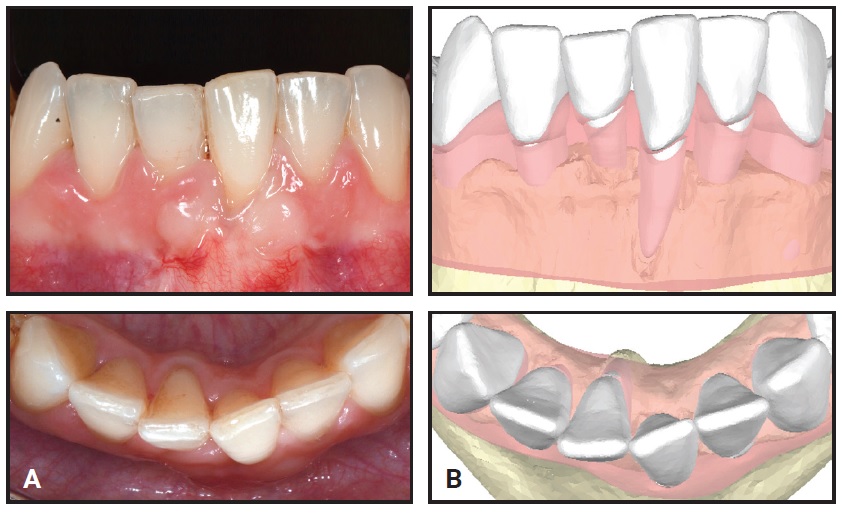

A 32-year-old female was evaluated by a periodontist and referred to the Department of Orthodontics at the University of Bologna (Fig. 2). She requested correction of her poor esthetics and relief from the marked dental sensitivity caused by gingival recession on the lower left central incisor, which seemed buccally displaced. The patient’s general dentist had tried to cover the recession, but advised that the tooth needed to be extracted. CBCT showed the root of the lower left central incisor outside its buccal cortical bone and the root of the lower right central incisor outside its lingual cortical bone (Fig. 3).

Fig. 2 A. 32-year-old female patient with gingival recession on buccally displaced lower left central incisor before treatment. B. Digital scan.